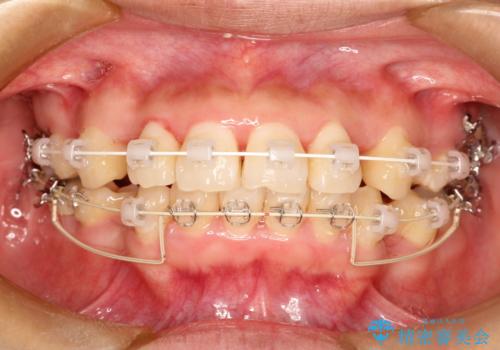

上下の歯のガタガタ ワイヤーでの抜歯矯正で整った歯並びへ

- 矯正装置

- 上下の歯のガタガタを治したいとのことで来院されました。

がたつきの度合いが強いのと、口元をなるべく引っ込めたい希望がありましたので、ワイヤーでの抜歯矯正となりました。

抜歯スペースを使って前歯を引っ込めることにより、口元の突出感も改善できました。